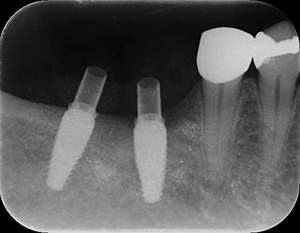

インプラント治療の症例4

レントゲン写真

- Befor

- After

| 年齢 | 50代・男性 |

|---|---|

| 主訴 | 部位:左下6番7番 主訴:左下奥歯腫れて痛い。 |

| 治療内容 | 左下6番抜歯、左下6番7番骨造成、インプラント埋入 |

| 治療費 | 合計:1,232,000円 ・内訳 診断料:55,000円 サージカルガイド2本:66,000円 GBR:110,000円×2本 埋入料:165,000円×2本 静脈内鎮静麻酔:77,000円 2次OPE:22,000円×2本 仮歯:55,000円×2本 上部構造(フルジルコニア):165,000円×2本 (2023年1月現在) |

| 治療期間 | 約8ヶ月 |

| 治療方針 | 元々支台歯に負荷がかかりやすいとされている延長ブリッジを抜歯し、1本単体でしっかりかめるようにインプラントを2本埋入した。骨吸収も進んでいたため、※GBR法で骨造成を同時に行った。 治療と並行して、全顎的な歯周病治療も行い、今後は歯周病が進行しないよう、こまめにメンテナンスに通っていただく。 |

| 特記事項 | ※1 GBR・・・骨再生誘導法。骨の高さや厚みを人工骨や人工膜などを使用し再生する方法 |

| 担当者所見 | 6番は歯根分割された被せ物が7番の欠損部との延長ブリッジとされており、強い咬合と歯周病も相まって負荷がかかり動揺し、歯として機能しなくなったため、抜歯となった。 |